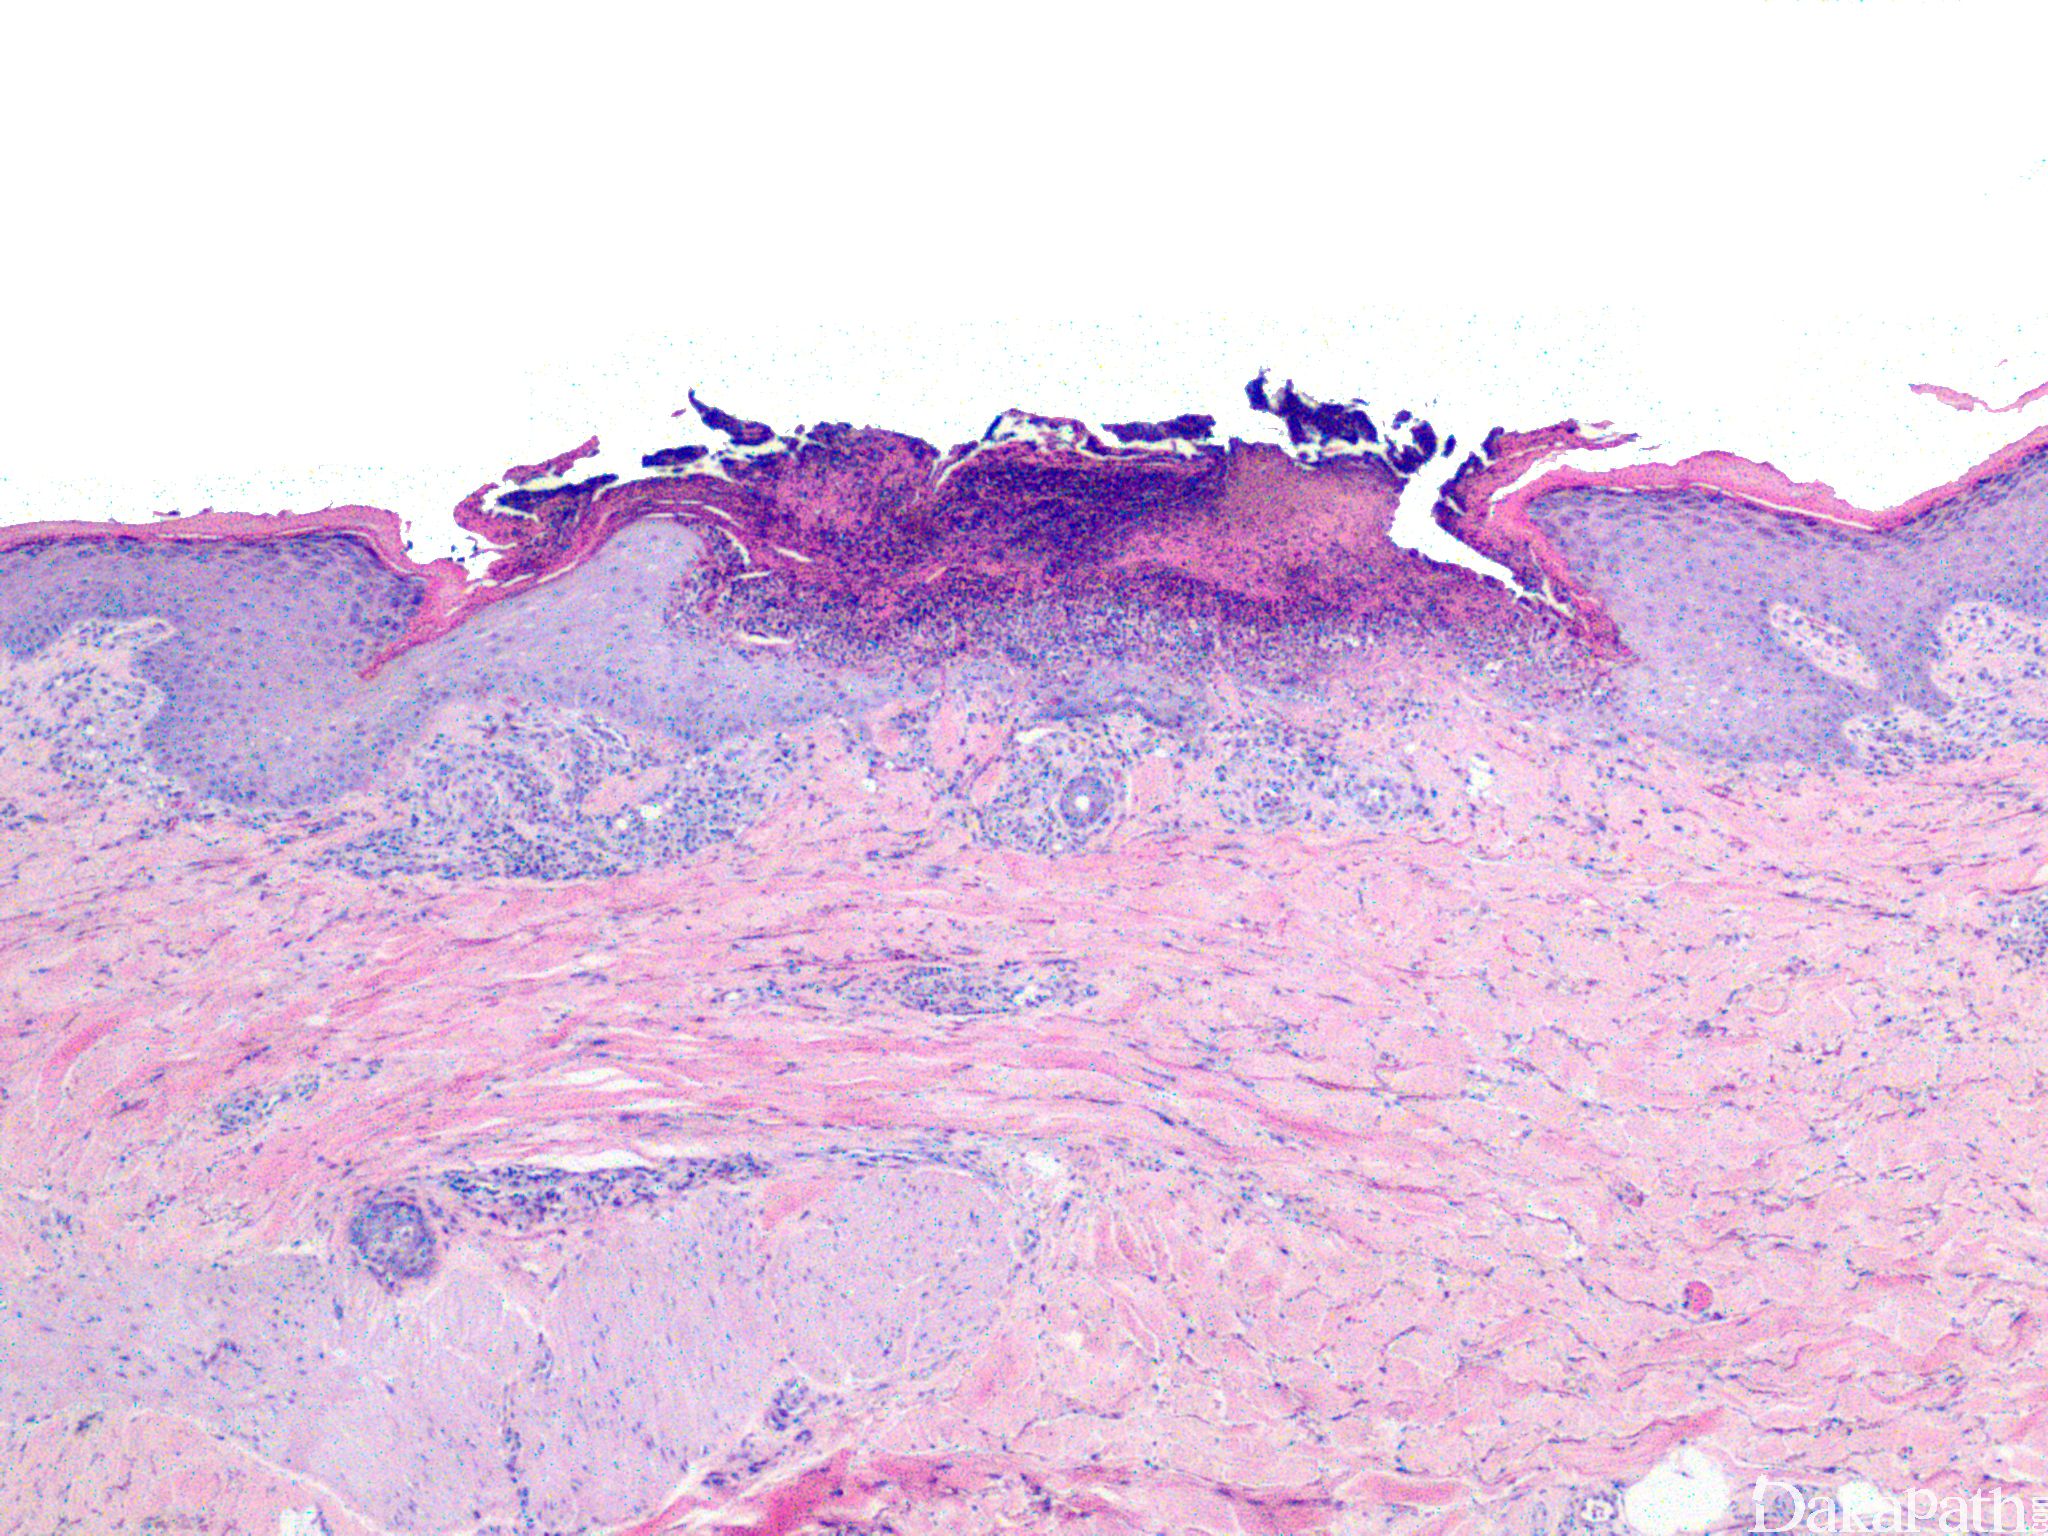

反应性穿孔性胶原病

reactive perforating collagenosis